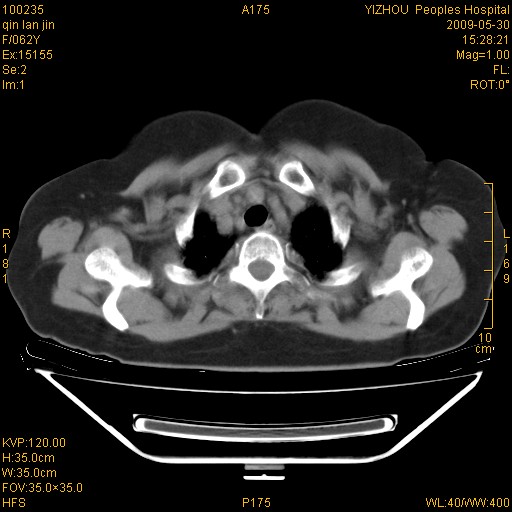

标题: CT20268:肺泡癌?间质性肺炎? [打印本页]

标题: CT20268:肺泡癌?间质性肺炎?

女,62岁,近二年经常咳嗽,近二个月,消瘦、乏力。

纵隔淋巴结大,须排外癌性淋巴管炎